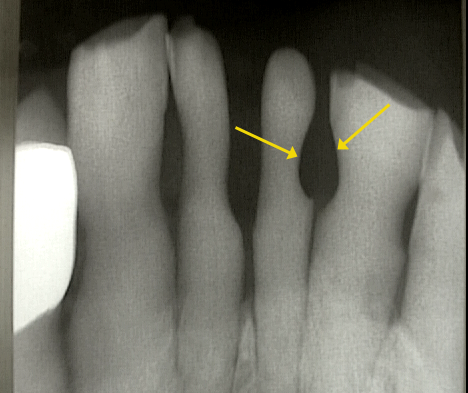

ブラッシングで歯周病は治ると指導され、動く歯を指で支えながらブラッシングを行ない定期的に受診。しかし、うがいの水もすごくしみ、歯の動揺のため咀嚼困難となりFDCを受診。

Phot―3.、Xray―1.からブラッシングによる歯の摩耗(黄矢印)が確認できる。

この症例も「ブラッシング教」信者の悲劇といえる。

自明のことであるが補助手段のブラッシングによって症状は一時的に改善するが

「歯周病が治癒」することはない。

現在、転院されてくる手遅れの患者さんを診ていますと日常的に行なわれている定期検査の在り方に多大な疑問を感じます。同様にブラッシング指導についても熱心な指導はよいとしても指導効果の検証がされていないために患者さんの歯の摩耗が多々みられます。